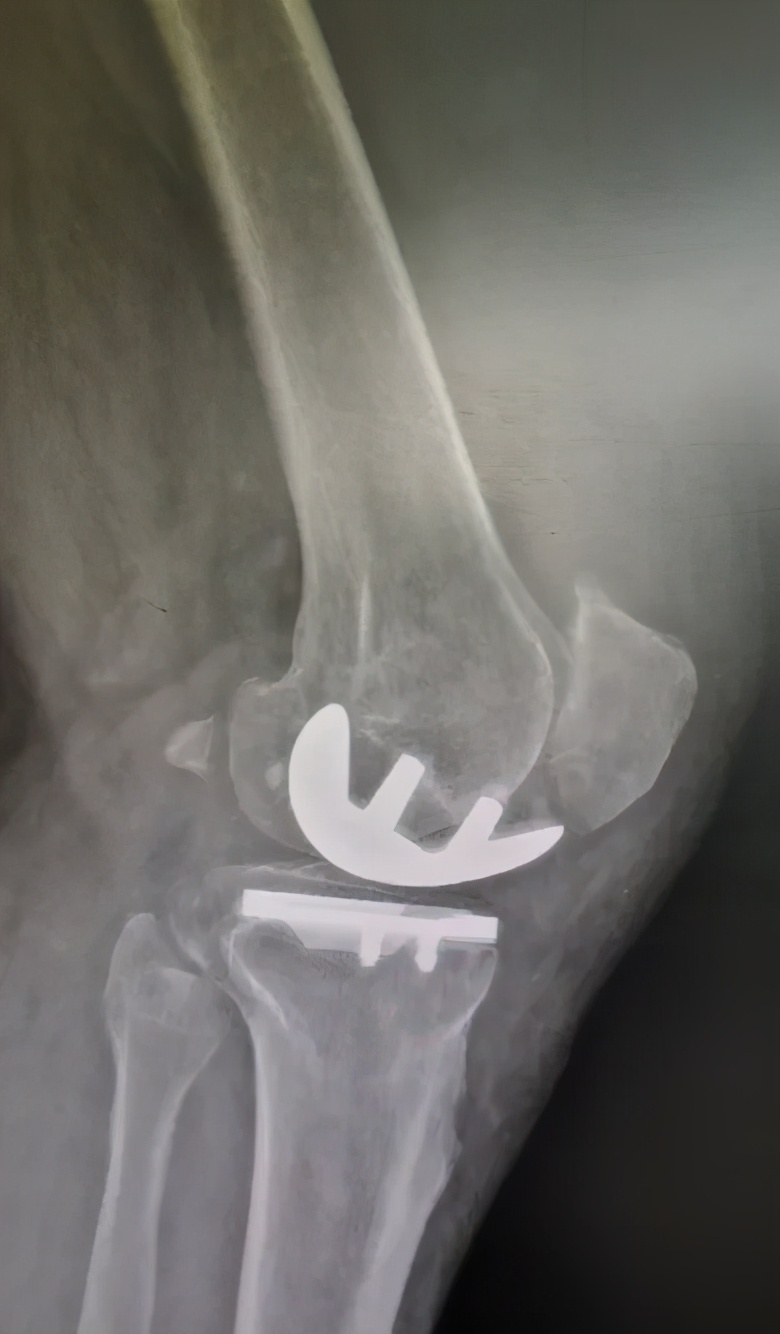

刘万军主任与团队讨论后指出,患者左膝关节内侧间室关节软骨破坏严重,外侧间室相对完好,适合膝关节单髁置换,并制定了详细的手术方案。术后患者症状消失,恢复良好。

( 术后一个月 )